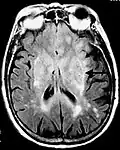

Postcontrast FLAIR of a case of meningitis. It shows enhancement of meninges at the tentorium and in the parietal region, with evidence of dilated ventricles.